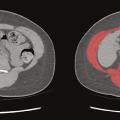

Les recommandations de la Haute Autorité de santé (HAS) publiées en 2019 ont reconnu la diminution de la force et/ou de la masse musculaire comme un critère phénotypique de la dénutrition.1 Parmi les outils recommandés chez l’adulte de moins de 70 ans figure l’évaluation de la surface musculaire en imagerie scanner. Néanmoins,…